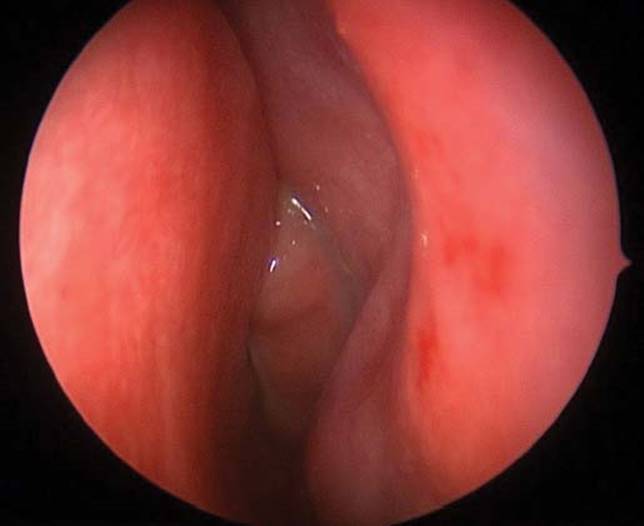

Figure 8.1 Endoscopic view of middle concha with sinusitis findings.

Flexible fiberoptic nasal endoscopy is feasible in any age when using a small diameter pediatric endoscope and may show drainage from the osteomeatal complex (Fig. 8.1) or sphenoethmoidal recess and can verify the diagnosis.11 Imaging studies are not recommended as part of the work-up of pediatric ABRS and cannot differentiate between viral URI and ABRS.2 When orbital or intracranial complications of ABRS are suspected then contrast-enhanced computed tomography (CT) scan should be obtained.